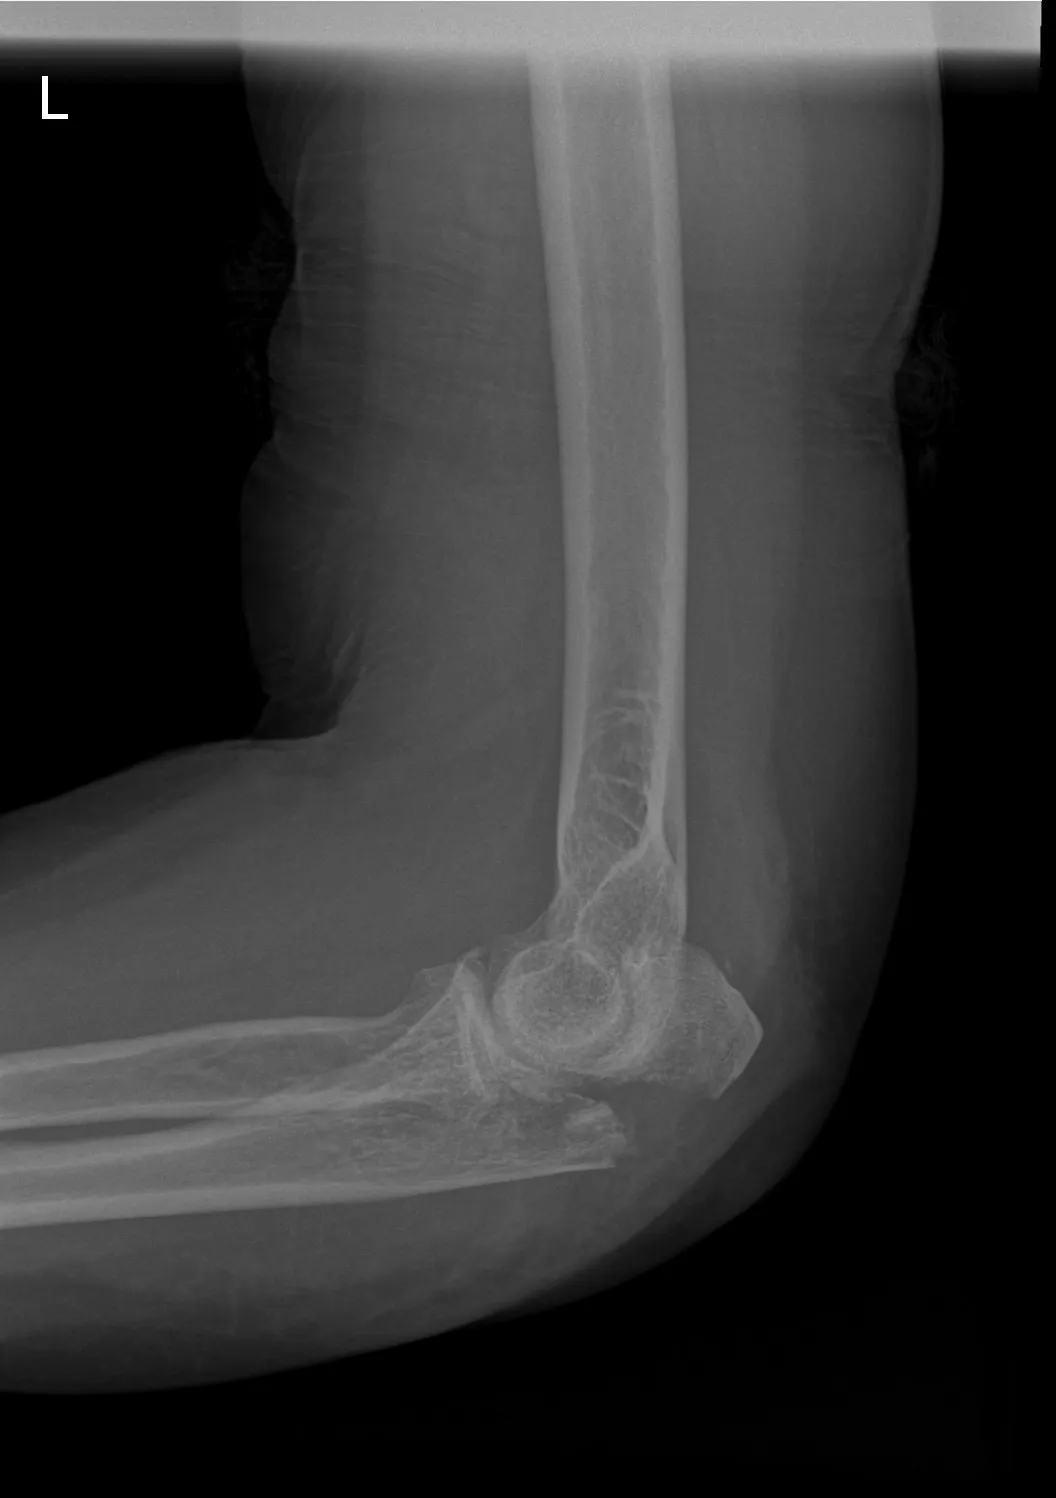

- Technisch onderzoek: Een röntgenfoto bevestigt de diagnose olecranonfractuur. Hierop is te zien of de elleboogbreuk verschoven is en hoeveel fragmenten er zijn. Soms wordt een CT-scan gemaakt om de breuk in detail te beoordelen, vooral als een operatie overwogen wordt.

Een olecranonfractuur is een specifieke elleboogbreuk: de botbreuk zit in het uitstekende deel van de ellepijp (ulna) aan de achterzijde van de elleboog, het olecranon. Met andere woorden, bij een olecranonfractuur is er sprake van een breuk van de ellepijp ter hoogte van de elleboog. Aan het olecranon zit de pees van de triceps (de grote strekspier van de bovenarm) vast. Wanneer dit deel gebroken is, kan de functie van deze spier (het strekken van de arm) verstoord zijn. Een olecranonfractuur ontstaat meestal door een val direct op de punt van de elleboog of door een harde klap tegen de elleboog.